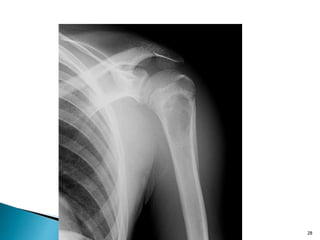

26

27

DR.KIRAN KAILAS

28